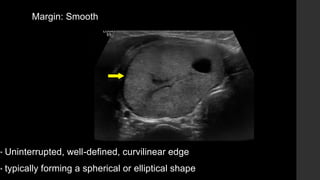

Margin: Smooth

• Uninterrupted, well-defined, curvilinear edge

• typically forming a spherical or elliptical shape